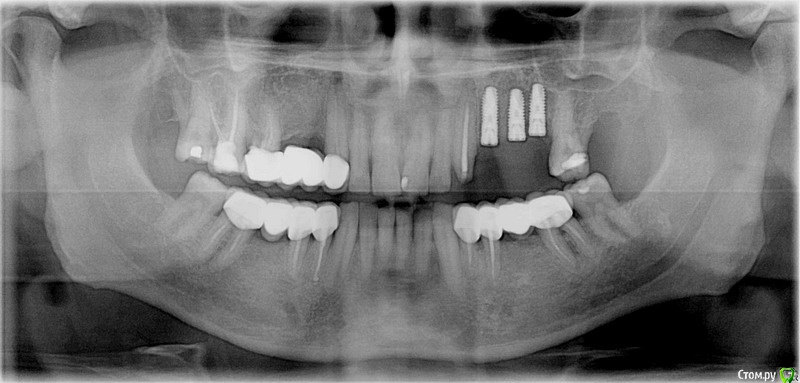

Анестезиолог Опубликовано 27 августа, 2017 Поделиться Опубликовано 27 августа, 2017 Пришло время менять мост на имплантаты (как видите, шестёрка справа сверху никуда, кажется это №16, есть симптоматика периодонтита уже неделю, еле-еле успокоил а/б и Нурофеном).Хирург посмотрел снимок и обратил внимание на стоящие уже. Прокомментировал следующим образом: "Надо было ставить не три импланта, а два, так как из-за того, что они стоят близко - средний и дистальный - нарушено питание костной ткани и она уходит. Кроме того, на названных имплантах слитные коронки, смысла в этом нет, только ухудшает гиг. мероприятия. Я поставлю два ипланта и мост на 3 единицы на них. Коронка на клыке останется временно, потом переставим".Вопросы:1. Правда ли, что есть ошибка в первой имплантации?2. Возможно ли не менять коронку на клыке? Жалоб писать ни на кого не собираюсь, судиться тоже, ответы не выйдут за рамки темы, просто мне для информации и планирования дальнейшей жизни части жевательного аппарата. Панорамные снимки моей улыбки в динамике прилагаю. Ссылка на комментарий

kriokov Опубликовано 27 августа, 2017 Поделиться Опубликовано 27 августа, 2017 только по пункту 1.близковато друг к другу имплантаты вкручены, кость соответственно уходит. Т.е переводя на русский, средний имплантат можно было не вкручивать. Убыль кости у Вас не от того, что не сделаны одиночные коронки на имплантатах. При адекватном расстоянии между имплантатами мосты с опорой на каждый имплантат хорошо работают, и долго. 5 Ссылка на комментарий

brg Опубликовано 27 августа, 2017 Поделиться Опубликовано 27 августа, 2017 (изменено) под промывным сверху с другой стороны тоже кость ушла. посмотрите первый и последний снимки. Изменено 27 августа, 2017 пользователем brg 1 Ссылка на комментарий